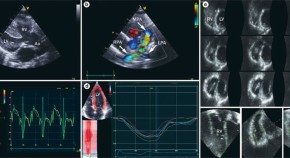

• Congenital defects of the heart affect up to 10 in 1,000 neonates, but mortality has decreased with improved detection and treatment. Drs Roest and de Roos describe the various imaging modalities available to assess patients with congenital heart disease before intervention, and to evaluate systolic, diastolic, valvular, and vascular function during follow-up.